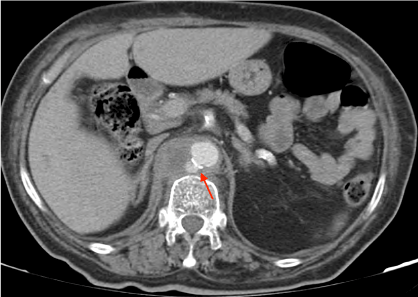

A 72-year-old female with multiple cardiovascular risk factors (hypertension, obesity, diabetes), peripheral artery disease (with amputation of both lower limbs), and chronic kidney disease on haemodialysis through an arteriovenous fistula, presented with a 2-month history of increasing low back pain radiating to the right abdominal quadrants. These complaints motivated a very recent in-hospital evaluation, with no defined aetiology after an extensive study. She also had multiple hospital admissions in the previous 6 months due to recurrent bacteraemia caused by different microorganisms. On admission, fever and increased inflammatory markers were documented (C-Reactive Protein 155 mg/L; 12400 leucocytes/µL), with hemodynamic stability (blood pressure 148/62 mmHg; heart rate 89 bpm) and no evidence of organ failure. She had diffuse abdominal discomfort on physical examination, with no signs of peritoneal irritation. There was no evident source of infection on the initial study. Empirical therapy was started with broad-spectrum antibiotic, de-escalated to ceftriaxone 2 gr after identification of methicillin-sensitive Staphylococcus aureus (MSSA) in blood cultures. Despite the directed antibiotic treatment, the clinical and analytic responses were slow. Study with transthoracic and transesophageal echocardiogram excluded endocarditis. A lumbosacral spine MRI and thoracoabdominopelvic CT were performed, with no evidence of spondylodiscitis, but showing a periaortic lesion with 60 × 50 × 40 mm, posterior to the crura of the diaphragm, extending from the thoracoabdominal aortic transition down to the origin of the superior mesenteric artery. A 12 mm pseudoaneurysm was also noted, with imaging pattern suggestive of a MA (Figure 1 and Figure 2).

Figure 1: Mycotic Aneurysm (CT scan with intravenous contrast). View Figure 1

Angio-CT is currently the gold standard in the evaluation of patients with suspected MA. Conventional angiography is still one of the best techniques in the diagnosis of this entity but it is an invasive procedure and does not allow evaluation of potential extravascular disease [1,3]. Typical imaging findings include an eccentric saccular aneurysm with an irregular arterial wall, severe oedema and a surrounding inflammatory mass as in this case [1,3].